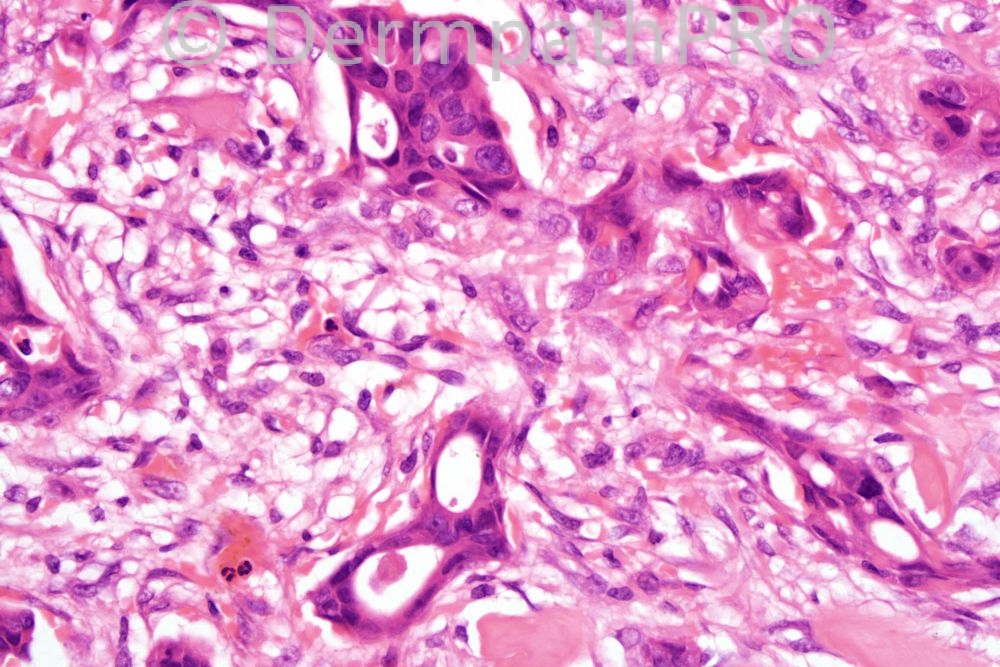

Male 71 years, clinically SCC ear.

Yes well done the diagnosis was Syringoid carcinoma with apocrine differentiation (MAC). I wish you all a happy New Year. Phillip will be taking over from tomorrow.

Microcystic adnexal carcinoma

?microcystic adnexal carcinoma (MAC) DD: desmoplastic trichoepithelioma